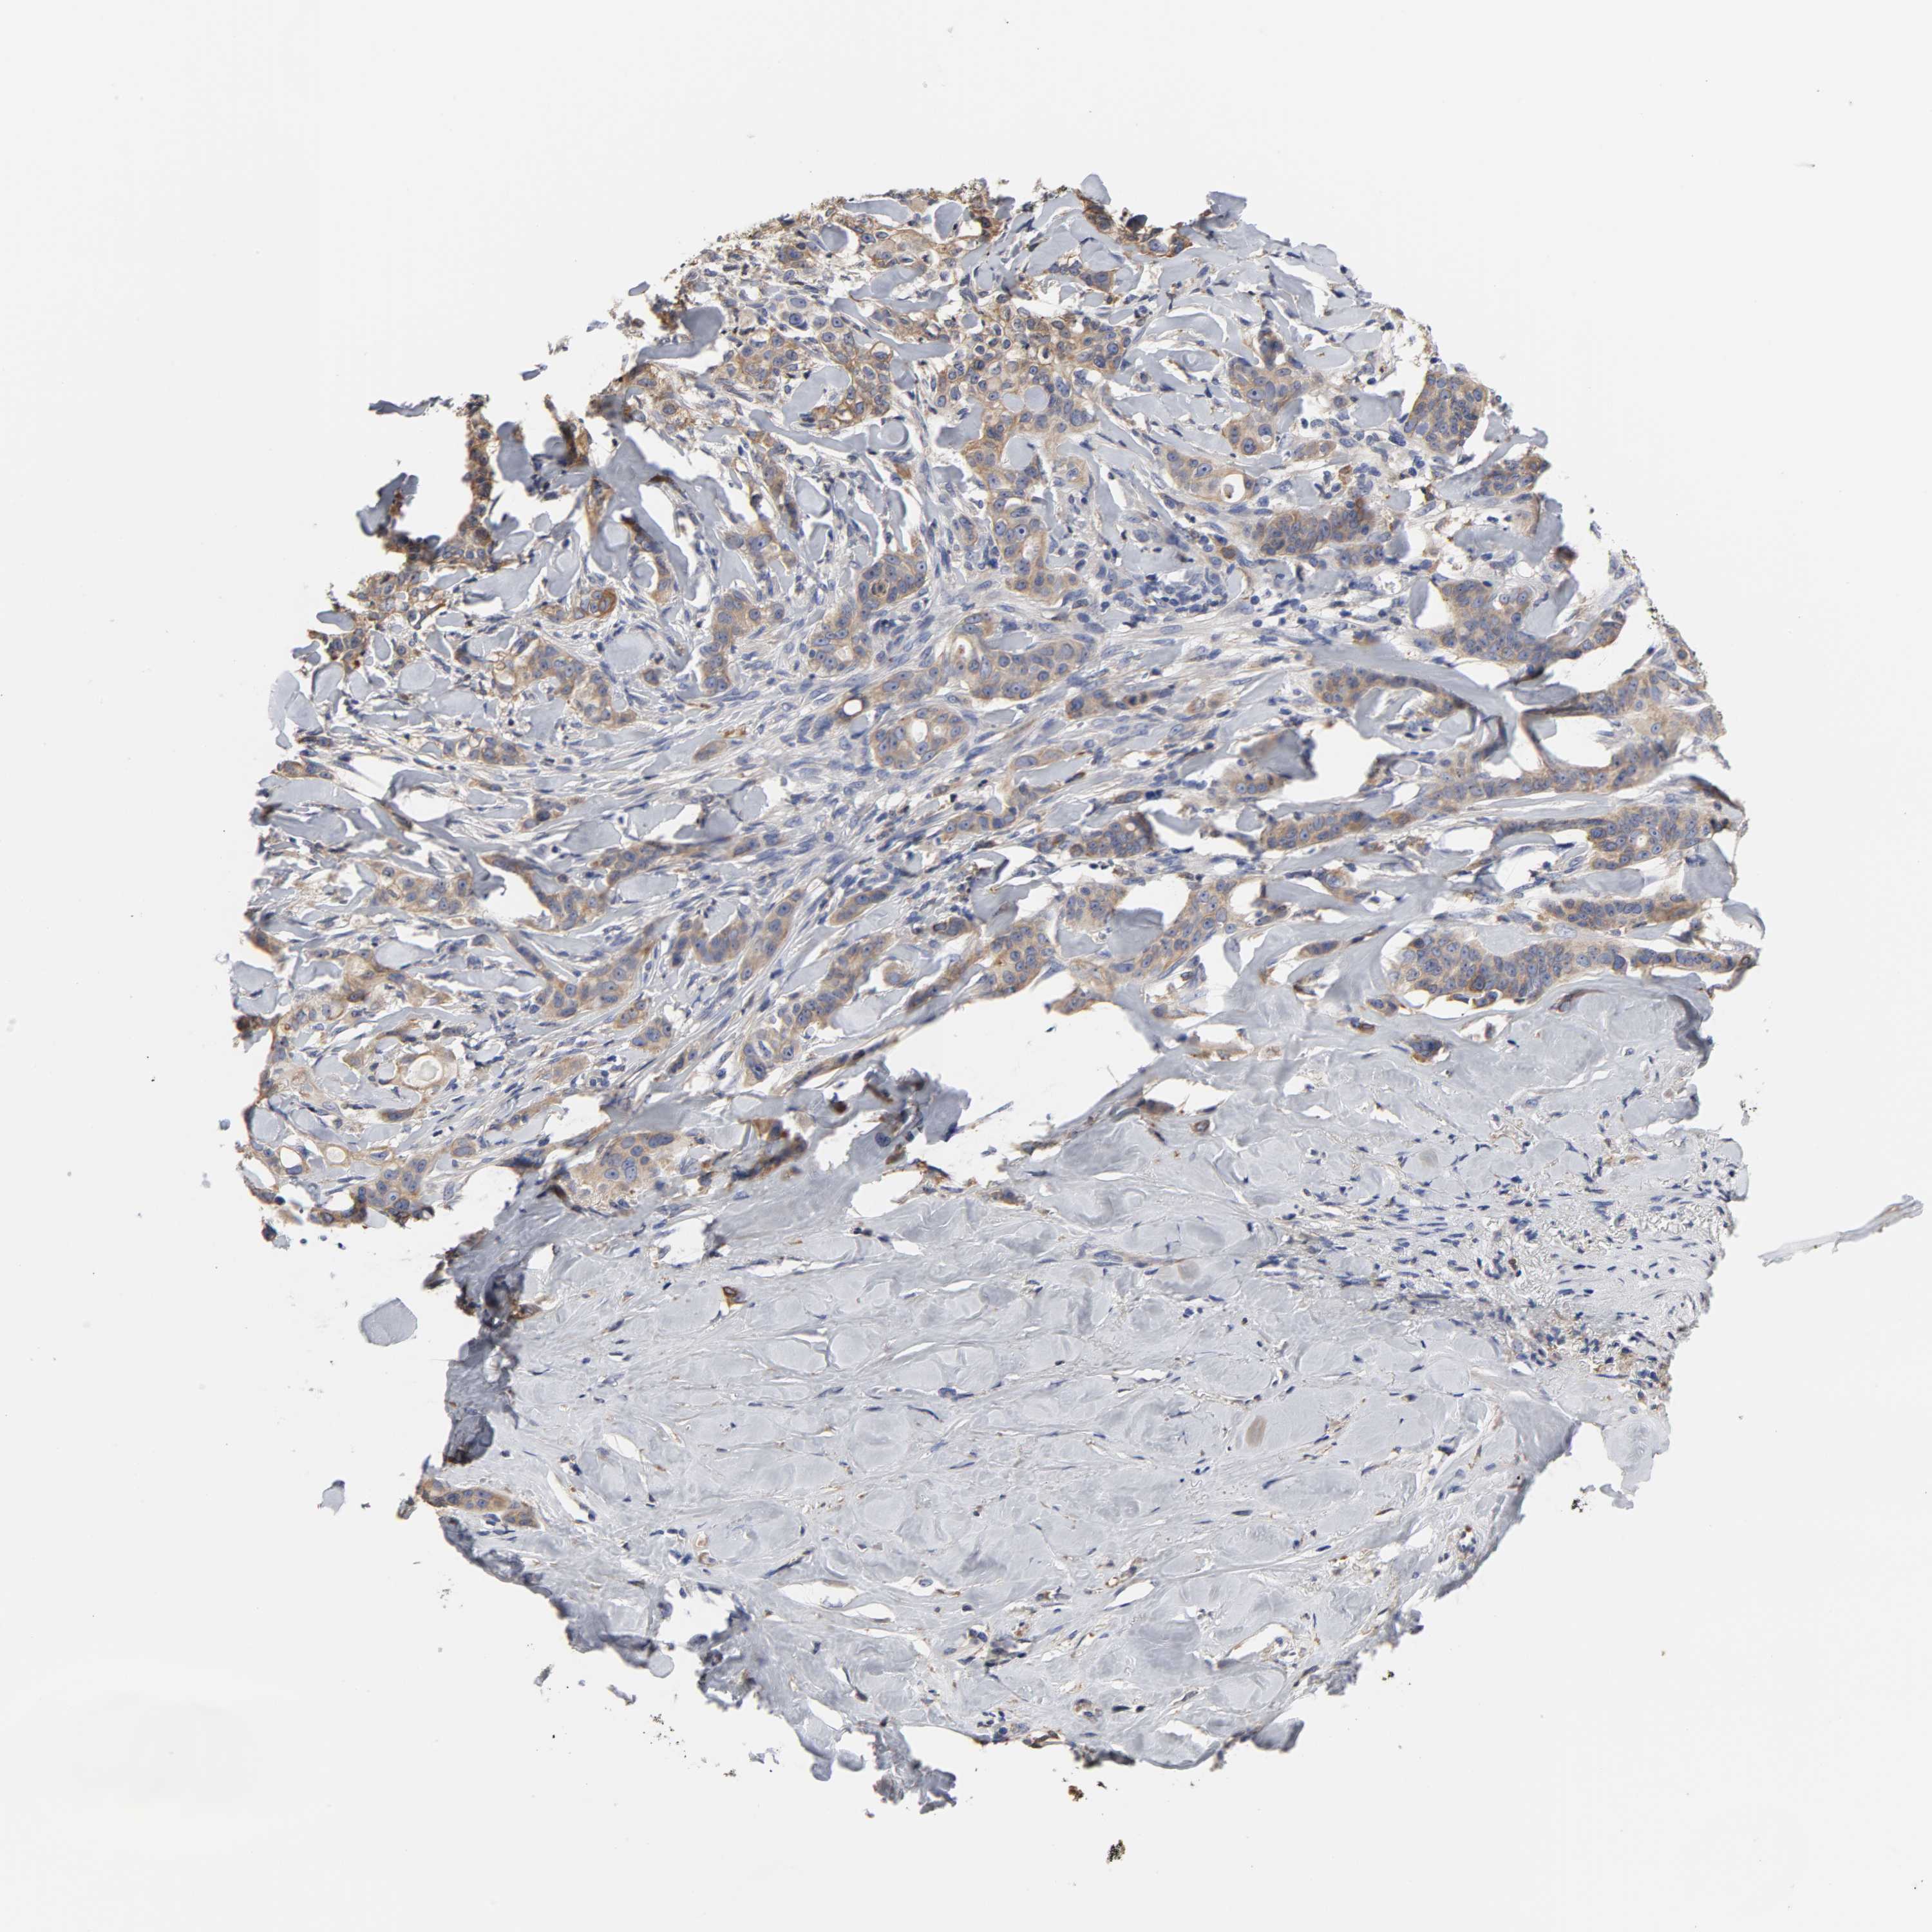

LIVER CANCER - Protein expressioni

A mouse-over function shows sample information and annotation data. Click on an image to view it in a full screen mode. Samples can be filtered based on level of antibody staining by selecting one or several of the following categories: high, medium, low and not detected. The assay and annotation is described here.

Antibody stainingi

Antibody staining in the annotated cell types in the current human tissue is reported as not detected, low, medium, or high, based on conventional immunohistochemistry profiling in selected tissues. This score is based on the combination of the staining intensity and fraction of stained cells.

Each image is clickable and will lead to virtual microscopy that enables deeper exploration of all samples and also displays staining intensity scores, fraction scores and subcellular localization as well as patient and tissue information for each sample.

Antibody CAB005195

Cholangiocarcinoma

Carcinoma, Hepatocellular, NOS